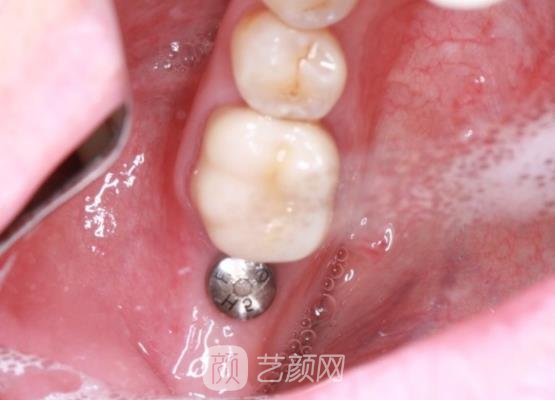

见到医生时,医生还积极的和我交流了一些手术知识,然后又让我了解了一些大概的手术流程之后,就帮我拍了口腔全片,又按照我的牙齿大小帮我制定了适合我的手术方案。

确定好方案以后手术就开始了,手术刚开始的时候我是真的很紧张的,尤其是打了麻药有一点痛感的时候,幸亏医生一直在旁边不断的安慰我,我紧张的情绪才缓解了很多,手术也是比较方便快捷的,几个小时以后就结束了。

刚结束手术时,我的牙龈处有一些疼痛的情况,而且还肿肿的,医生让我不用太过于担心,告诉我这些现象比较正常,又叮嘱我回家观察几天,如果几天以后牙龈处还是有着疼痛的情况,让我及时与他联系进行复诊。

果然现在我的牙齿已经恢复的很自然了,就像是我自己的牙齿一样,根本看不出来手术的痕迹,而且我的口腔里面也没有什么异物感,手术成果真的很棒,让我很满意。